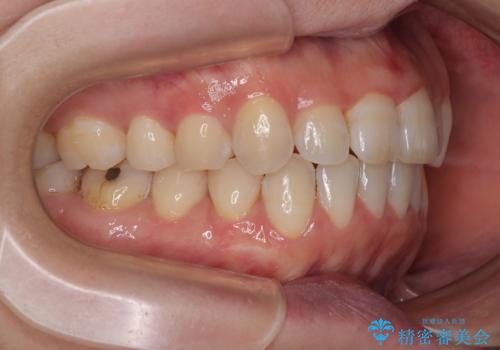

- 上下前歯が非接触となり、前方に突出していることを気にして来院された患者様です。

上下の前後差が大きいため、インビザライン単独での上顎歯列移動は困難と判断し、補助装置により上顎歯列を後方移動させ、その後インビザラインにて仕上げていくこととしました。

補助装置なしでも改善できる可能性はありましたが、補助装置で確実性を上げ、短期間できっちりと仕上げることができました。